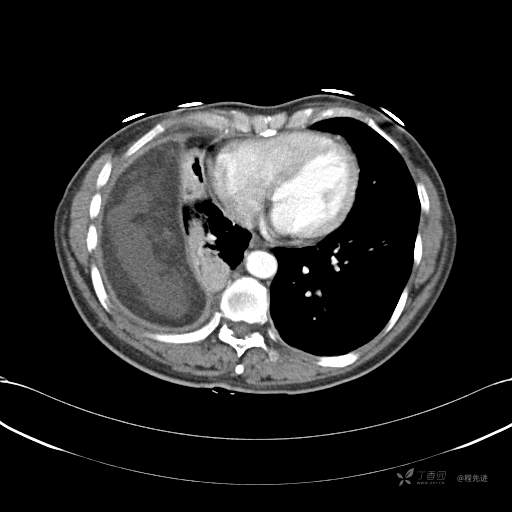

患者性别:女

患者年龄:51岁

简要病史:胸闷半年